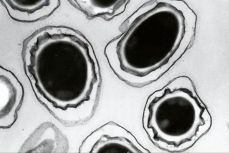

Investigan en EE.UU. envío accidental de ántrax por el Pentágono